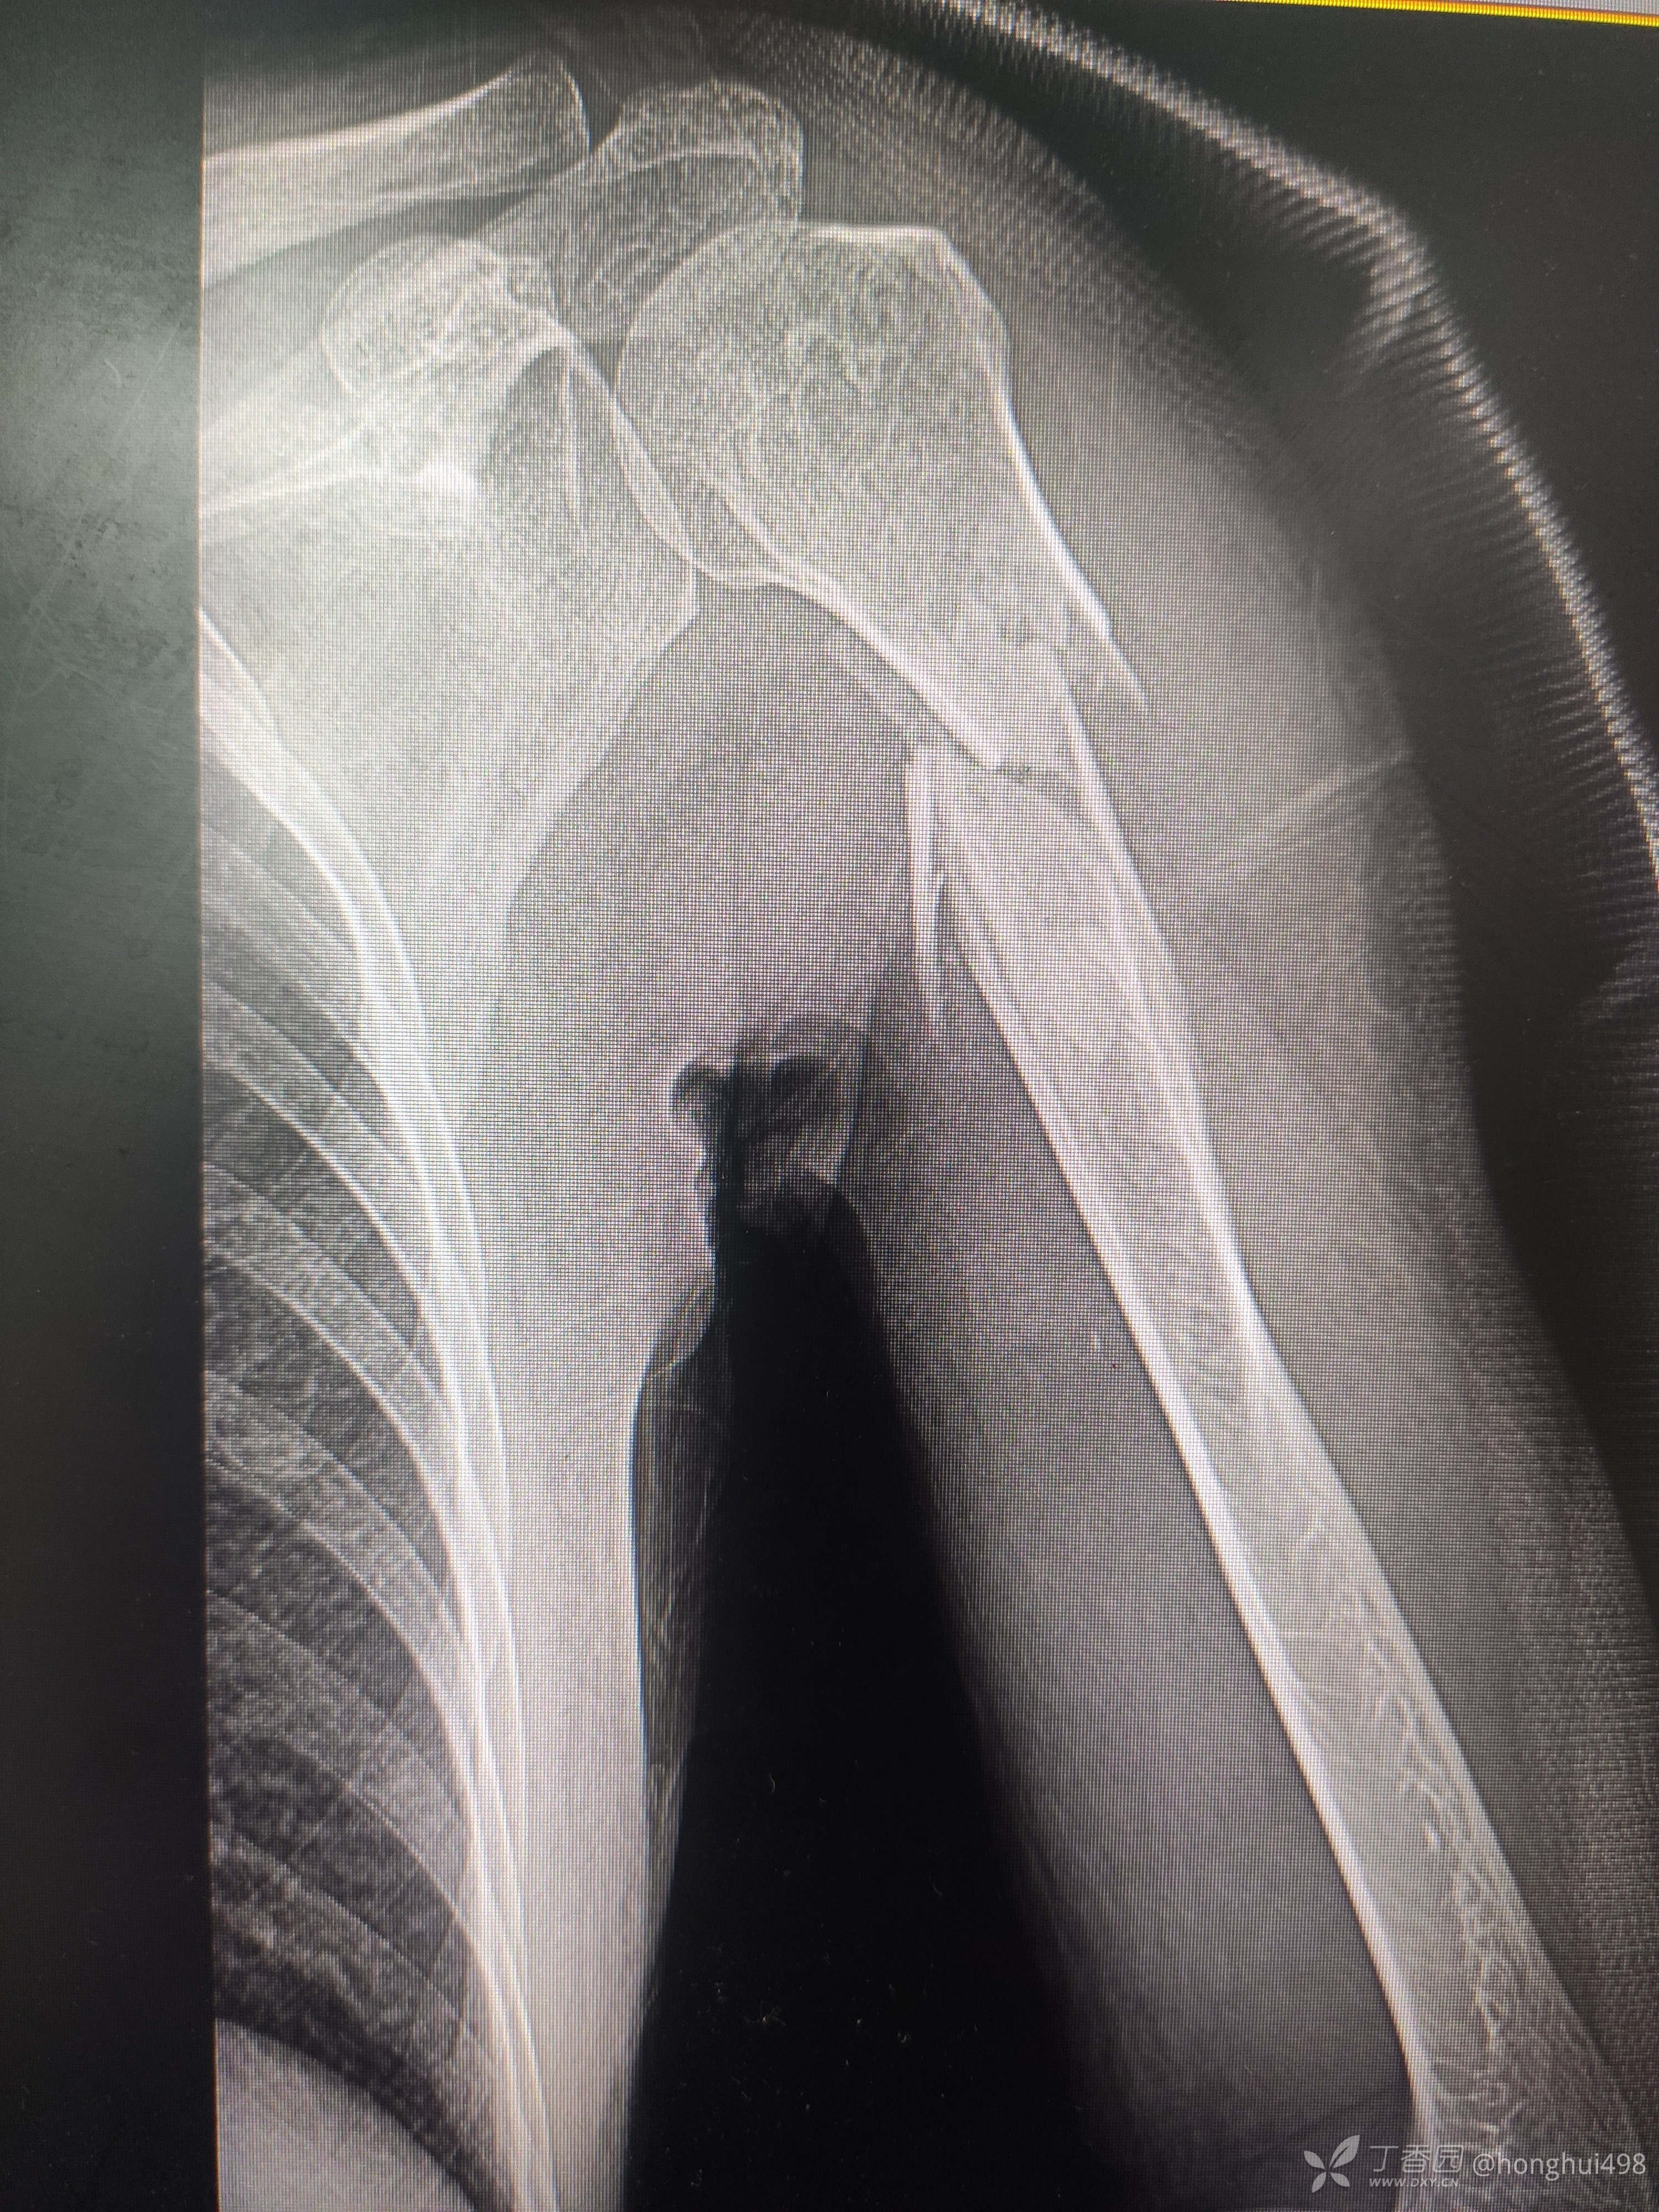

男性患者,62岁,摔倒致伤,入院诊断右肱骨骨折。麻醉下行肱骨骨折有限切开复位髓内钉+钢缆固定。

肱骨髓内固定做得比较少,但是手术还是顺利,此例患者你们如何选择固定方式?欢迎讨论